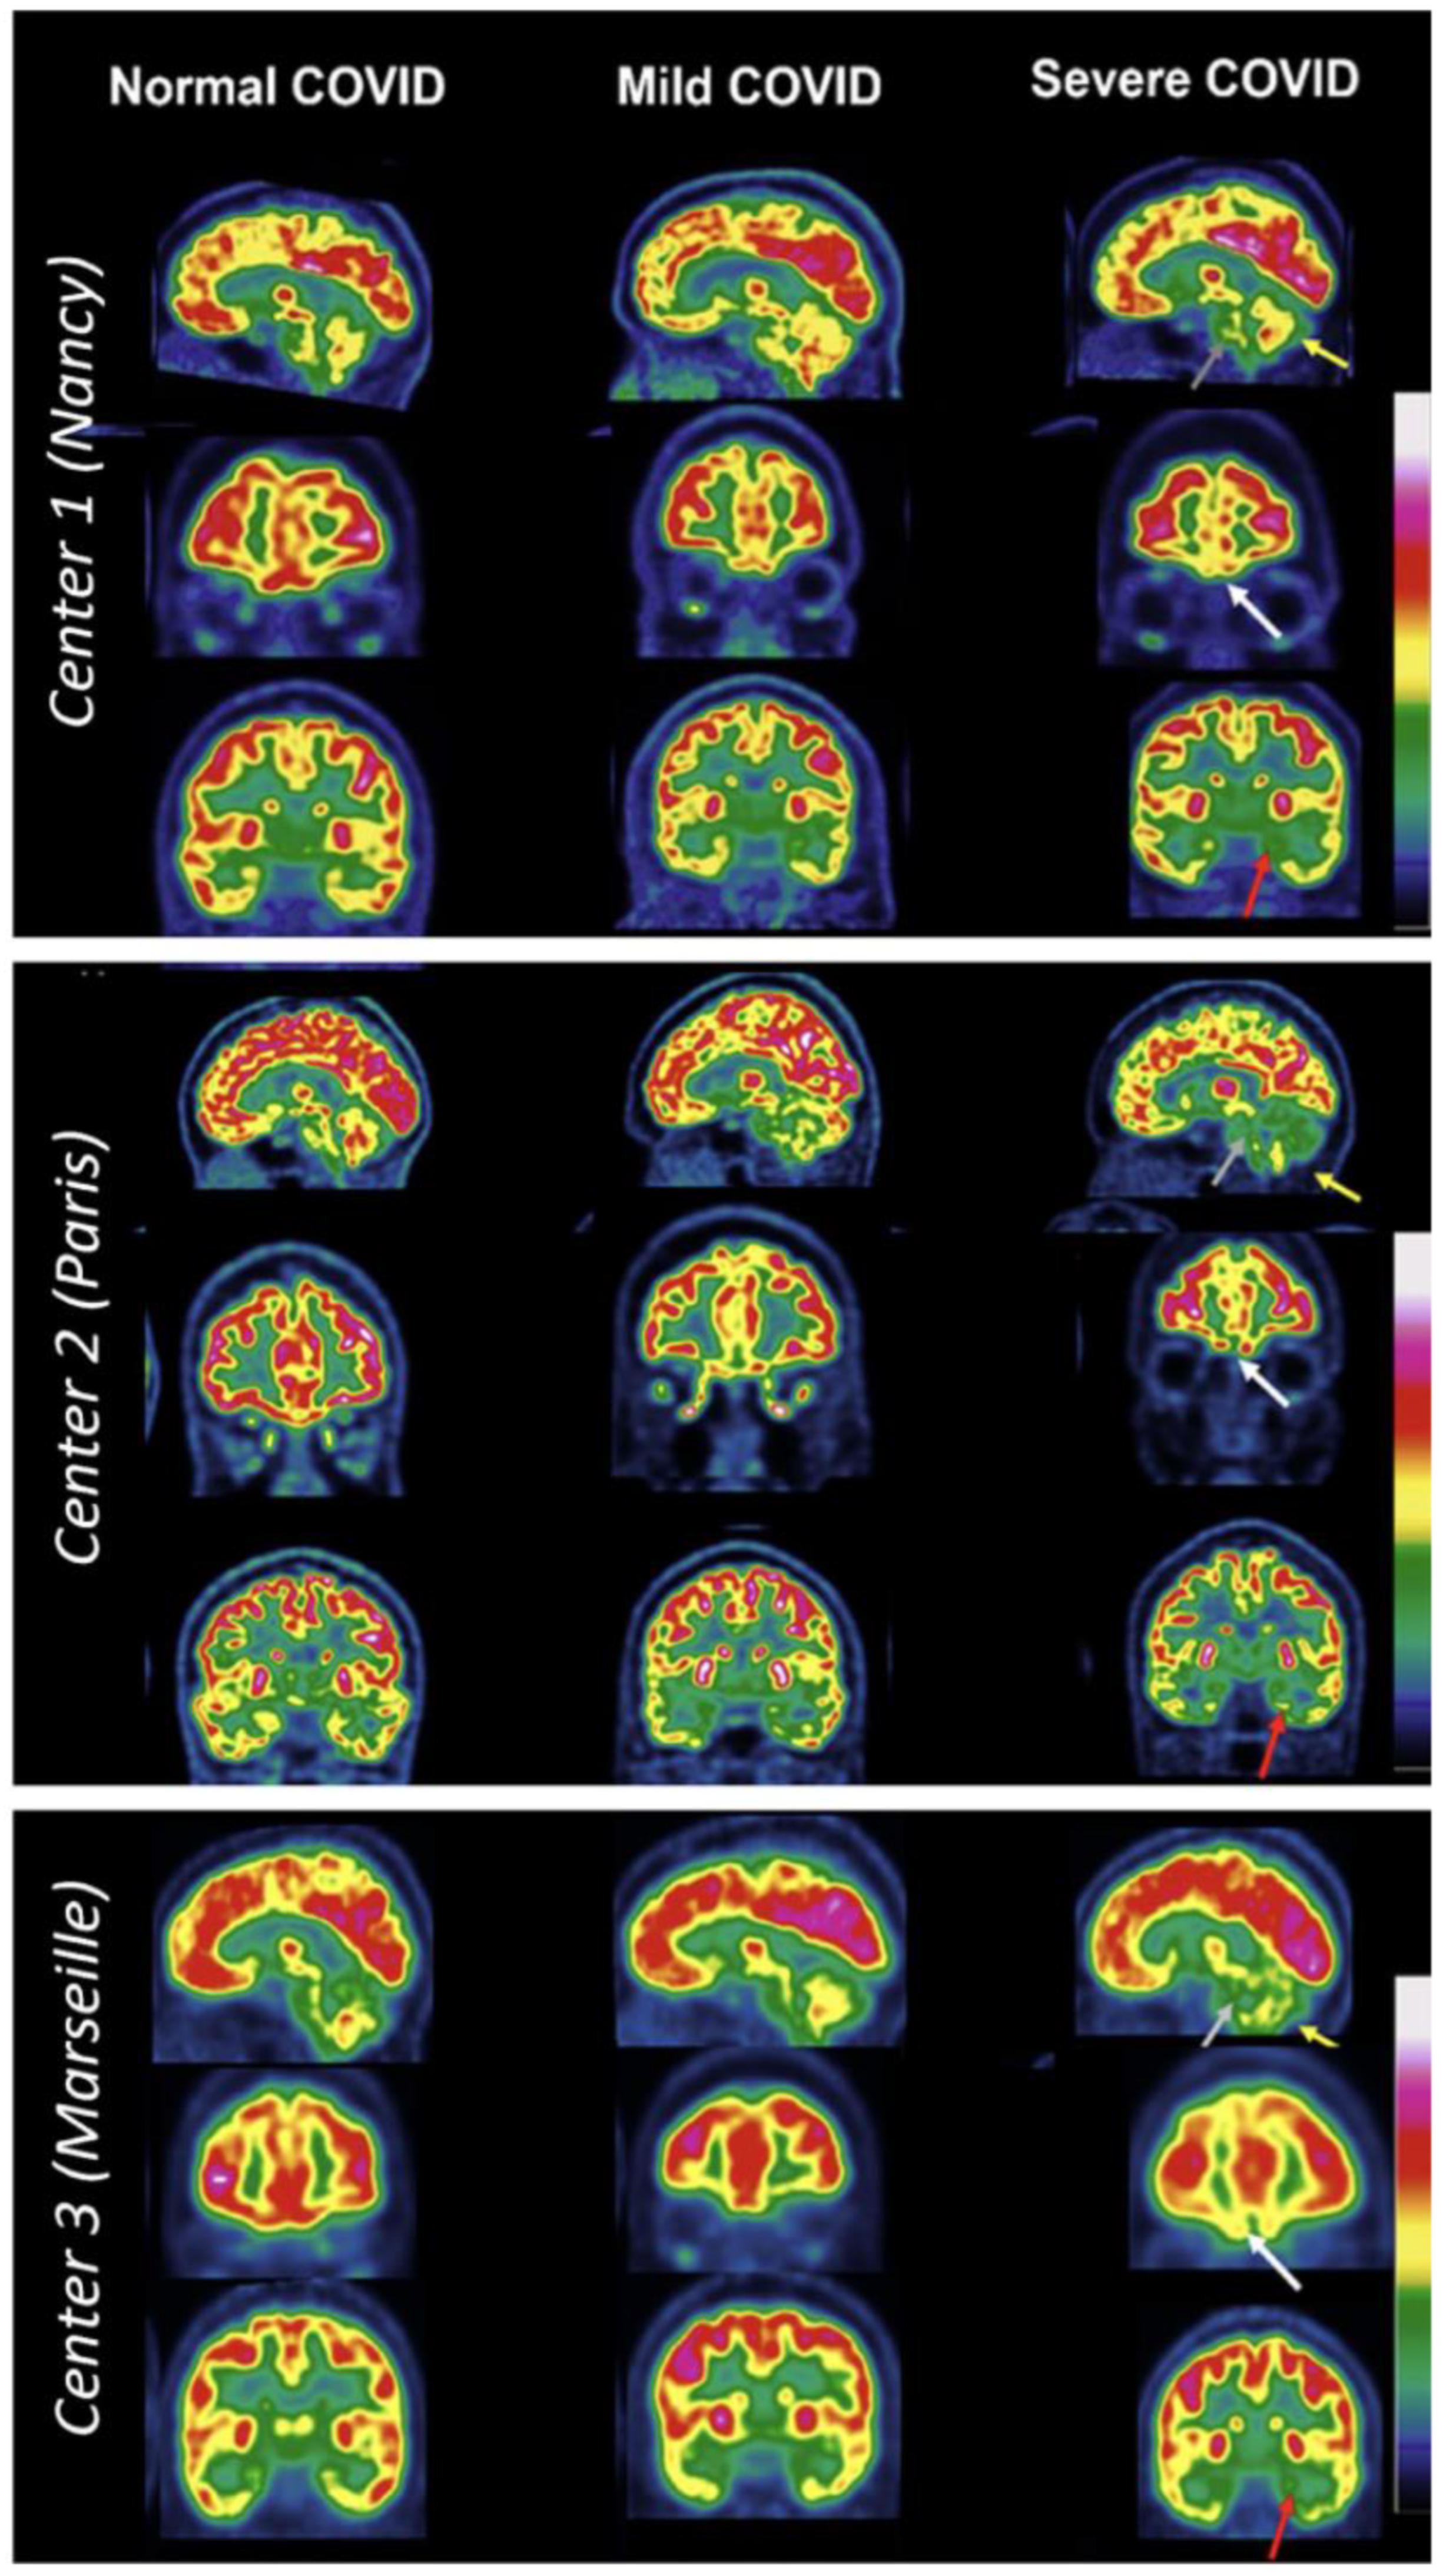

- Verger, A.; Kas, A.; Dudouet, P.; Goehringer, F.; Salmon-Ceron, D.; Guedj, E. Visual Interpretation of Brain Hypometabolism Related to Neurological Long COVID: A French Multicentric Experience. Eur. J. Nucl. Med. Mol. Imaging 2022, 49, 3197–3202. [Google Scholar] [CrossRef]

- Guedj, E.; Campion, J.Y.; Dudouet, P.; Kaphan, E.; Bregeon, F.; Tissot-Dupont, H.; Guis, S.; Barthelemy, F.; Habert, P.; Ceccaldi, M.; et al. 18F-FDG Brain PET Hypometabolism in Patients with Long COVID. Eur. J. Nucl. Med. Mol. Imaging 2021, 48, 2823–2833. [Google Scholar] [CrossRef]